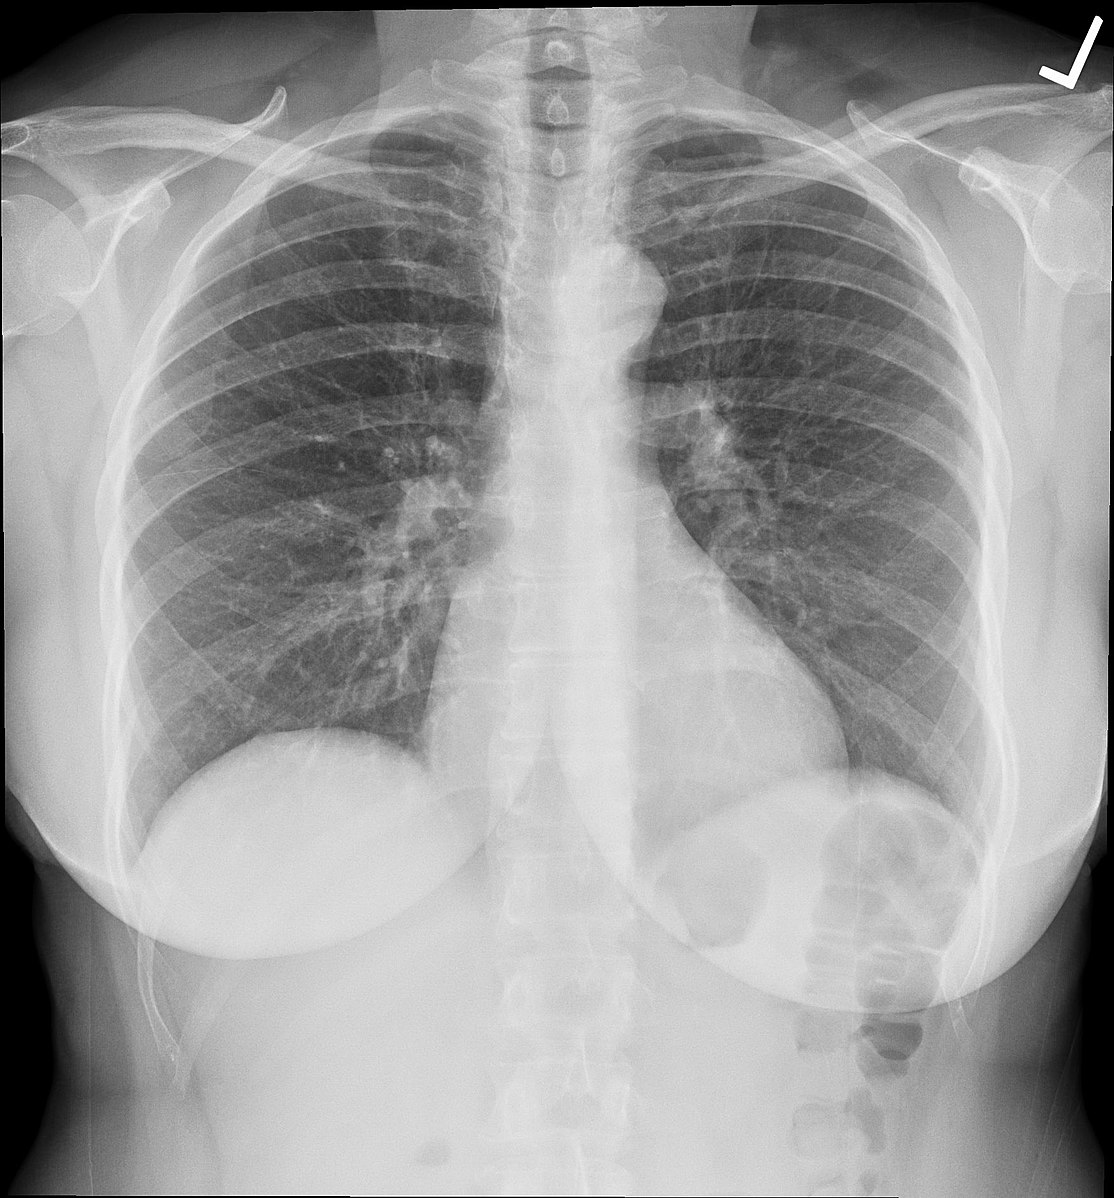

- X-rays

Chest X-ray (Normal). -